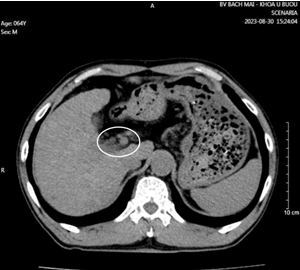

Hình 3: Nhu mô hạ phân thùy VII có vài khối, nốt kích thước lớn nhất 33x26mm giảm tỷ trọng trước tiêm, ngấm thuốc thì động mạch (vòng tròn đỏ), thải thuốc thì tĩnh mạch cửa (vòng tròn).

Cắt lớp vi tính ổ bụng có tiêm thuốc cản quang: